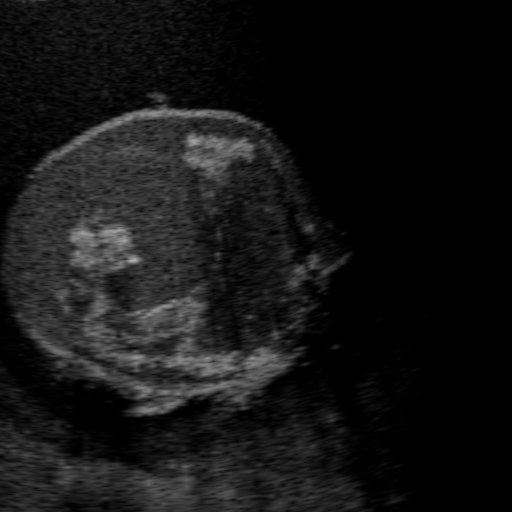

3.1 Full field-of-view Images

Above image translation has been demonstrated on patches. For the entire field-of-view (FoV) US images, patch fusion from image translation of non-overlapping patches would cause artifacts at image seams. Averaging overlapping patches, on the other hand, would blur the essential US texture. Although seamless tiling of US images is possible using graphical models [3], this requires prohibitively long computation time. Herein, we instead directly apply our trained generator on full FoV low-quality images, since the generator is fully convolutional and thus can operate on images of arbitrary size. Fig. 4 shows two examples of translated images by L2HMS and L2HMSA, demonstrating direct inference on full FoV images. While anatomical structures are well preserved and the effect of attenuation integral map is apparent, speckle texture appearance is seen to degrade slightly especially in the top image regions, where the ultrasound texture looking particularly different due to focusing difference and near-field effects.